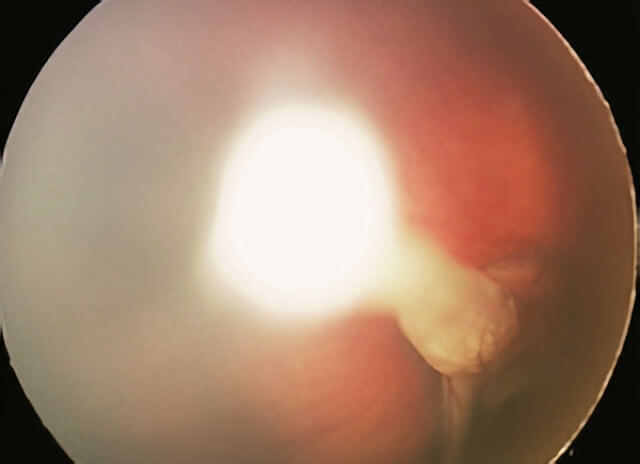

The most important disease to rule out when a child presents with leukocoria is retinoblastoma (a rare malignant tumor of the retina). Typically, if one is able to visualize the back of the eye, a stalk is seen spanning the space between the optic nerve and the back of the lens. If the view into the back part of the eye is challenging, ultrasound and/or CT/MRI scans are often performed.

For the typical child with PFVS who has leukocoria noted in one eye shortly after birth (after retinoblastoma is ruled out) surgical intervention should be considered for this visually significant disease. It is rare for an eye with PFVS requiring surgical intervention to be restored to normal vision. However, the anatomy and function can often be improved and the eye typically grows more normally with surgery.

Most commonly the lens is removed, and on occasion surgery is also done to reattach the retina. Replacement of the lens function typically requires use of a contact lens postoperatively, and patching therapy to minimize amblyopia is the norm.